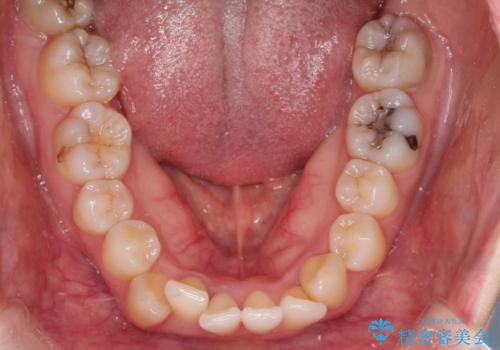

- 「歯のデコボコと前歯が出ているせいで口が閉じにくい」を主訴に来院された患者様です。

上下左右の4番(第一小臼歯)を抜歯をし審美ワイヤー装置で治療を行いました。

抜歯矯正により歯列のデコボコ(叢生)が改善し、前歯の突出も解消されたことで口元が下がり、すっきりとした印象となりました。